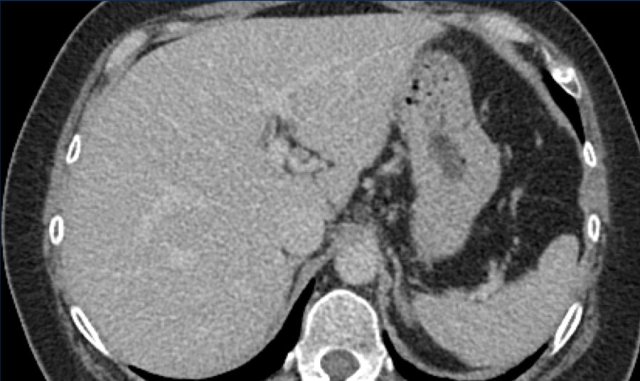

This is another patient with an enhancing lesion and washout.

Note also the enhancing capsule on the delayed phase.

A capsule is one of the major features of HCC and can be complete or partial.

A capsule should always be included within the measurement of the lesion.